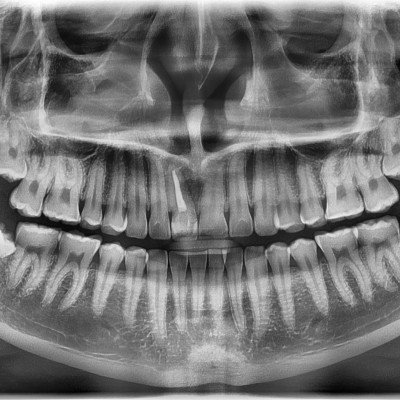

#28,38 사랑니 발치 #28,38 사랑니 발치 구강 외과 전문의가 당일 발치하였습니다. -------------------------..

작성자 이턱이 작성일 01-29 조회 5